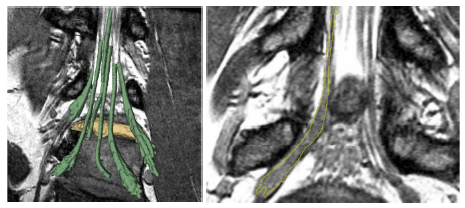

Patient data results. Left: Rendered segmentation results a herniated disk (manually segmented, yellow) is impinging on the nerve tracts (segmented with our algorithm with minimal user input, green). Right: Slice that includes a section of a nerve and a ganglion. The yellow outline indicates the automatic delineation of the nerve. The algorithm tends to slightly under-segment the nerve, as we see the margins of the nerve underneath the segmentation.